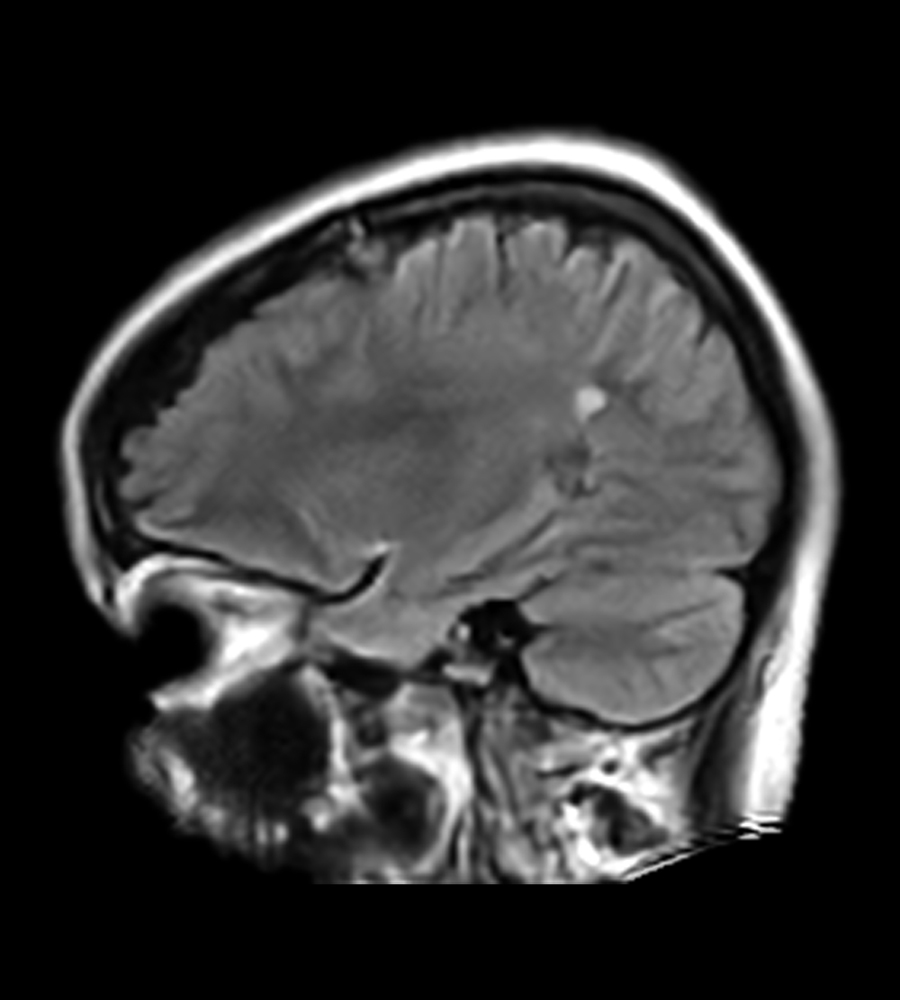

Clinical Images

Clinical Case Types: Headache, Migraine, Multiple Sclerosis, Microvascular Disease, and Tumor Routine Follow-up.

Headache